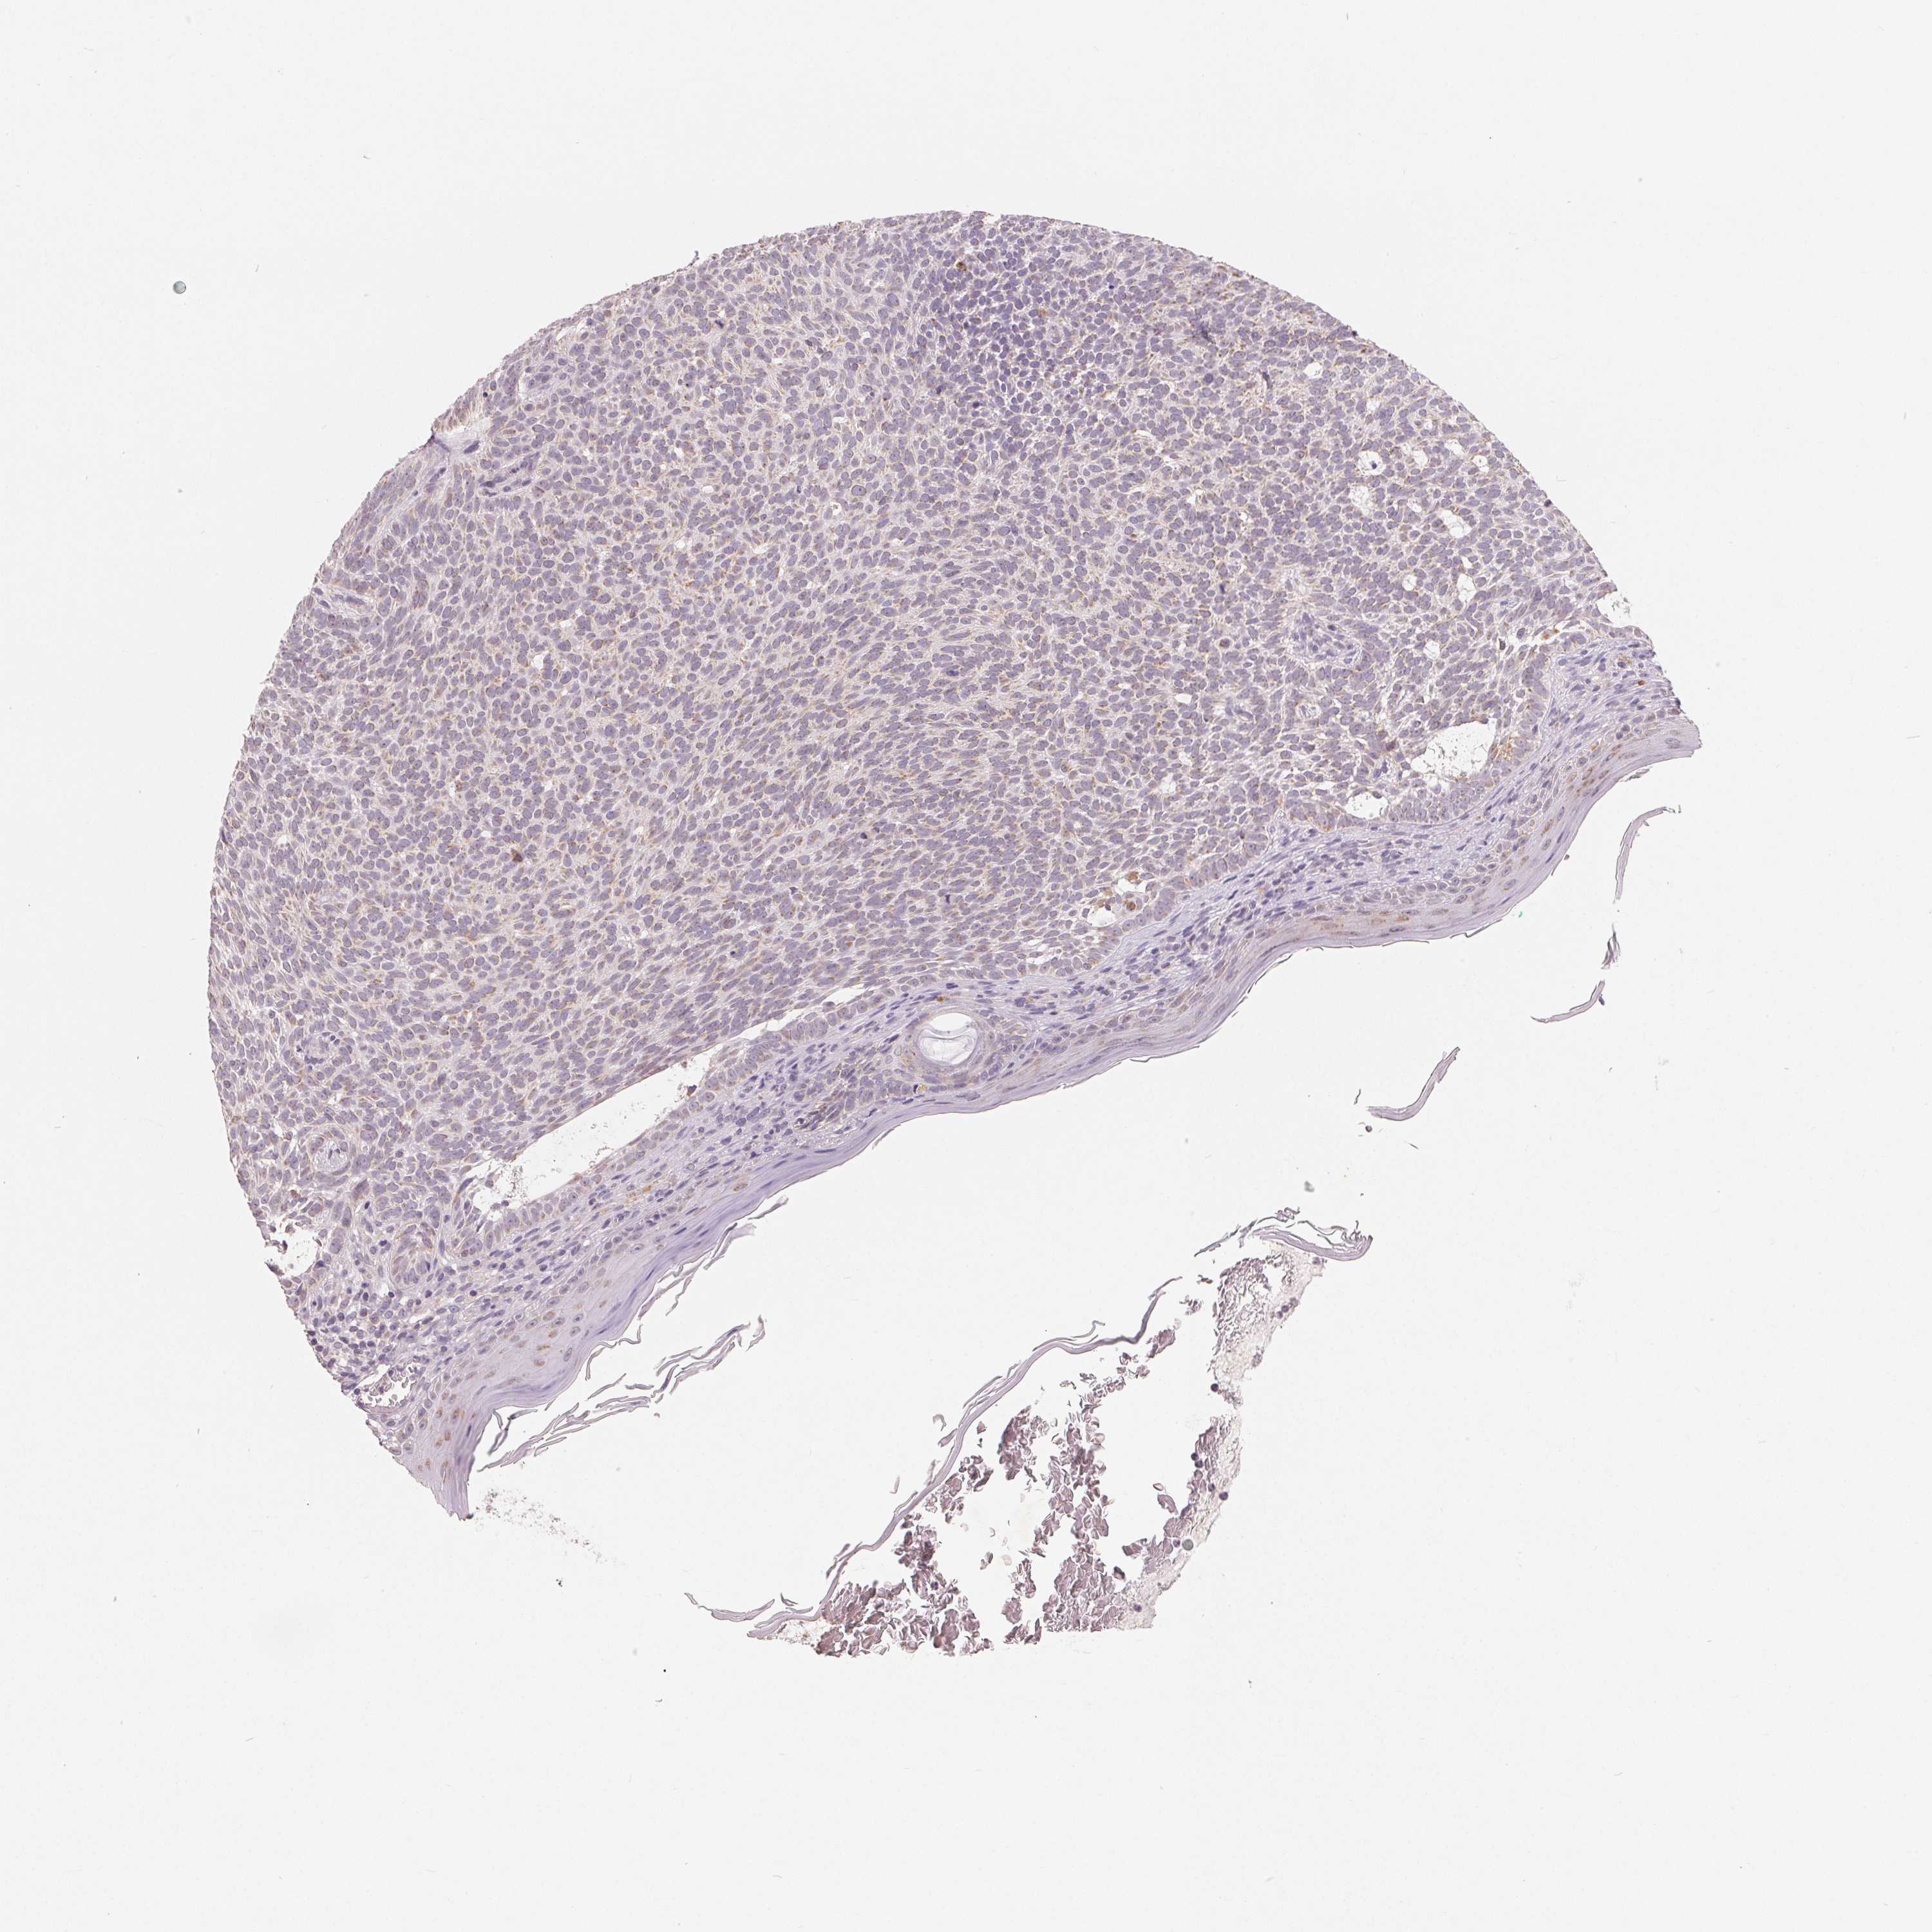

SKIN CANCER - Protein expressioni

A mouse-over function shows sample information and annotation data. Click on an image to view it in a full screen mode. Samples can be filtered based on level of antibody staining by selecting one or several of the following categories: high, medium, low and not detected. The assay and annotation is described here.

Antibody stainingi

Antibody staining in the annotated cell types in the current human tissue is reported as not detected, low, medium, or high, based on conventional immunohistochemistry profiling in selected tissues. This score is based on the combination of the staining intensity and fraction of stained cells.

Each image is clickable and will lead to virtual microscopy that enables deeper exploration of all samples and also displays staining intensity scores, fraction scores and subcellular localization as well as patient and tissue information for each sample.

Antibody HPA016464

Antibody HPA061664

Basal cell carcinoma

Squamous cell carcinoma, NOS

Squamous cell carcinoma, metastatic, NOS

BCC, high aggressive